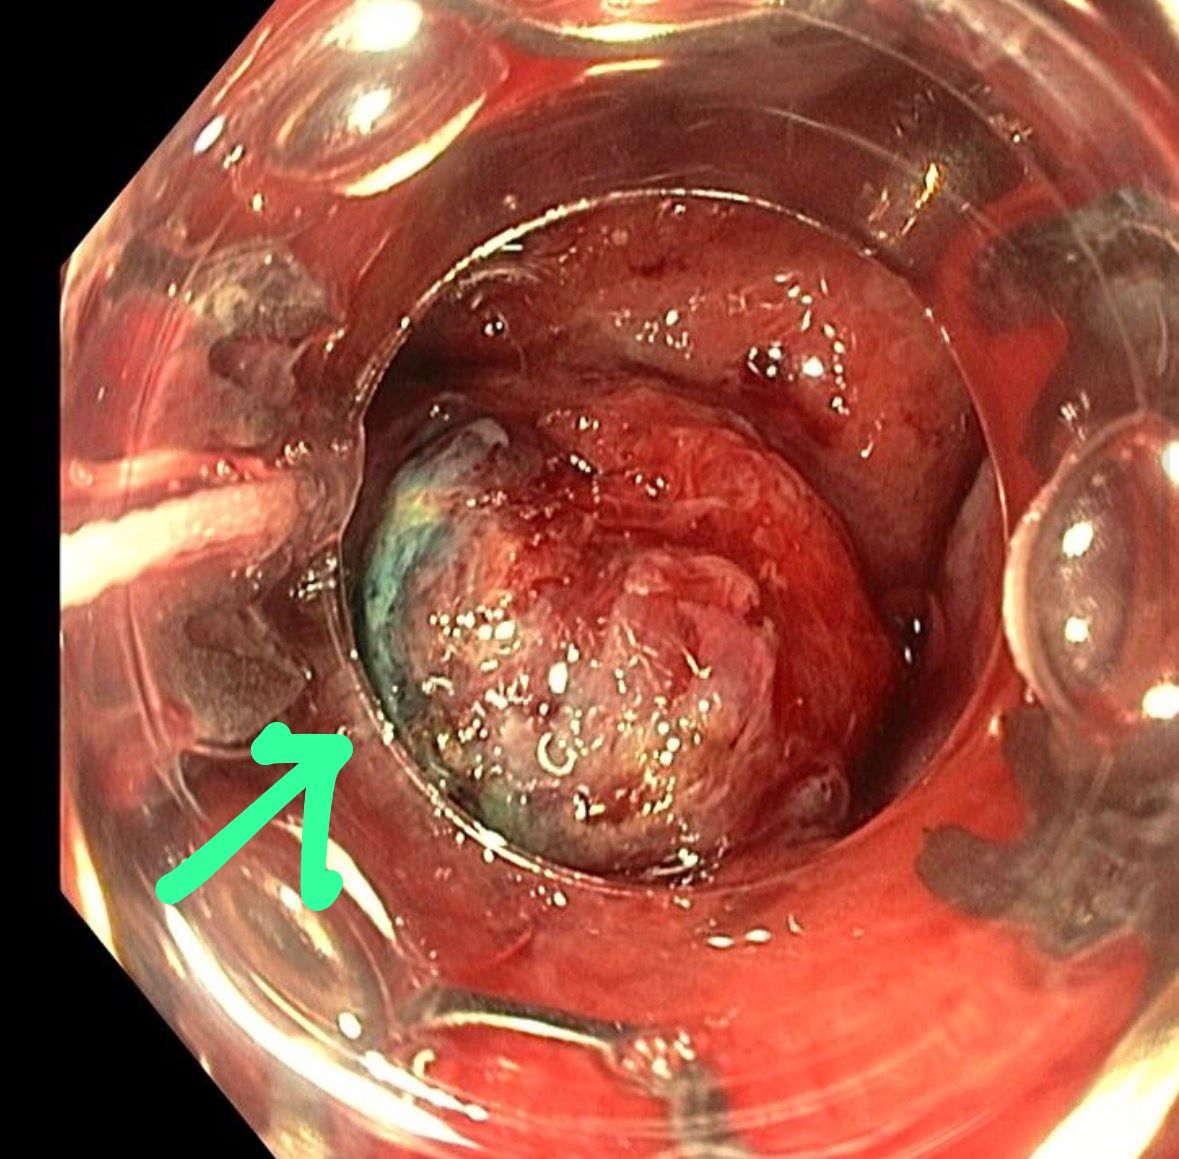

5. Rectal Lesion: Hyperplastic, Serrated, or Ectopic Gastric Mucosa?

A rectal lesion with uncertain endoscopic appearance. Initial reads favored hyperplastic or serrated sessile lesion. One member offered a different interpretation: ectopic gastric mucosa in the rectum, a rare finding that can cause rectal bleeding.

Two PubMed references were shared, including a published case report by a community member. Ectopic gastric mucosa is well known in the esophagus and Meckel’s diverticulum but rarely considered in the rectum.